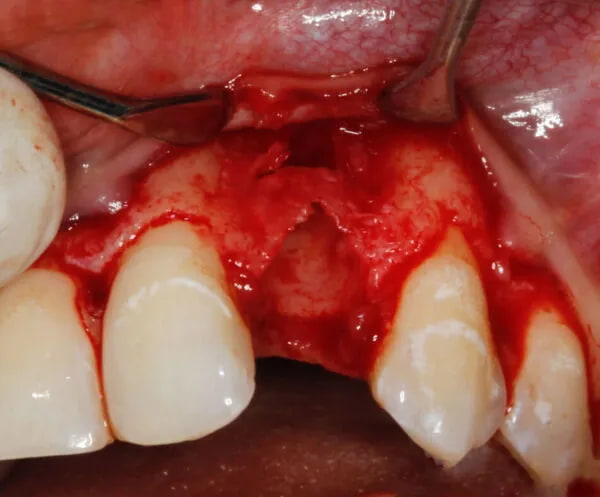

Regeneracja tkanek przyzębia

Zabiegi z zakresu periodontologicznej chirurgii regeneracyjnej pozwalają na pełne odtworzenie utraconych w przebiegu zapalenia przyzębia tkanek twardych i miękkich. Tym tym samym poprawiają rokowanie dotyczące zachowania zęba lub zębów.

- Czynniki wpływające na skuteczność leczenia regeneracyjnego ubytków kości w przyzębiu.

- Materiały stosowane w periodontologicznej chirurgii regeneracyjnej (przeszczepy, biomateriały, błony zaporowe, czynniki wzrostu).

- Strategie leczenia ubytków kości w przyzębiu.

- Minimalnie inwazyjne techniki chirurgiczne w leczeniu regeneracyjnym pionowych ubytków kości w przyzębiu: technika pojedynczego płata (SFA), technika podwójnego płata (DFA).

- Leczenie ubytków kości w przyzębiu w odcinku estetycznym: technika ściany przeszczepu tkanki łącznej (CTW), technika zachowująca całą brodawkę międzyzębową (EPPT), zabieg oczyszczenia przyzębia po podniesieniu płata (OFD).